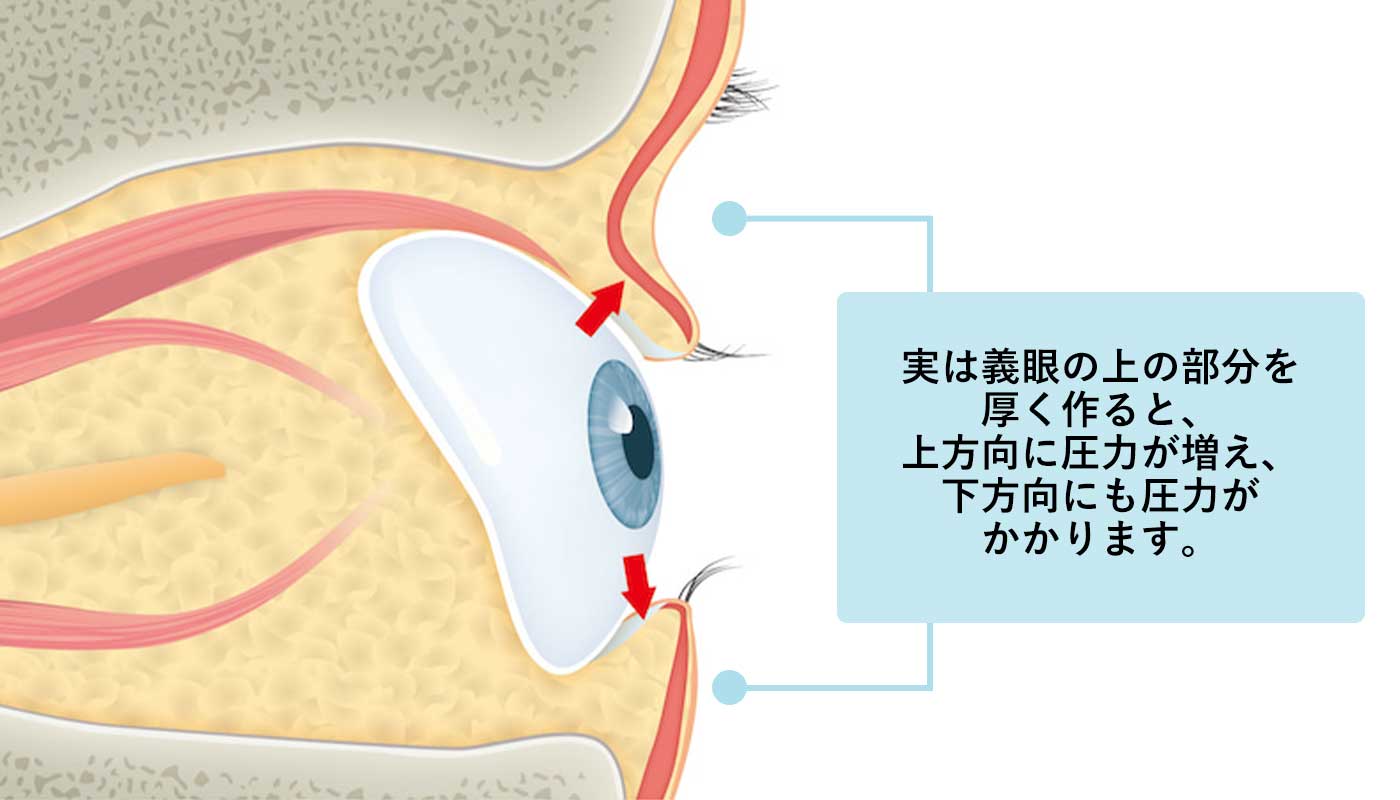

義眼を厚く作ると…

義眼師さんたちは上のまぶたのへこみを治す、もしくはまぶたが下がっているのを治すために、義眼の上の部分を厚く作り、上のまぶたのへこみを治そうとします。実は義眼の上の部分を厚く作ると、上方向に圧力が増えるのですが、下方向にも圧力がかかるのです。

つまり厚くなった義眼は上のまぶたを押し上げるだけでなく、その副作用として下のまぶたを押し下げてしまうのです。

これが2つ目の病態、下眼瞼下垂(下まぶたが下がる)と逆さまつげの原因となります。

義眼に下まぶたの結膜(しろめ)が押し下げられ、その結果としてまつ毛が内側に向いて逆さまつげになってしまいます。眼球の容積が減少したことに対応して、義眼を大きくしたためにこのようなことが起こってしまうのです。

眼球の容積が減少したことに対応して、義眼を大きくしたためにこのようなことが起こってしまうのです。